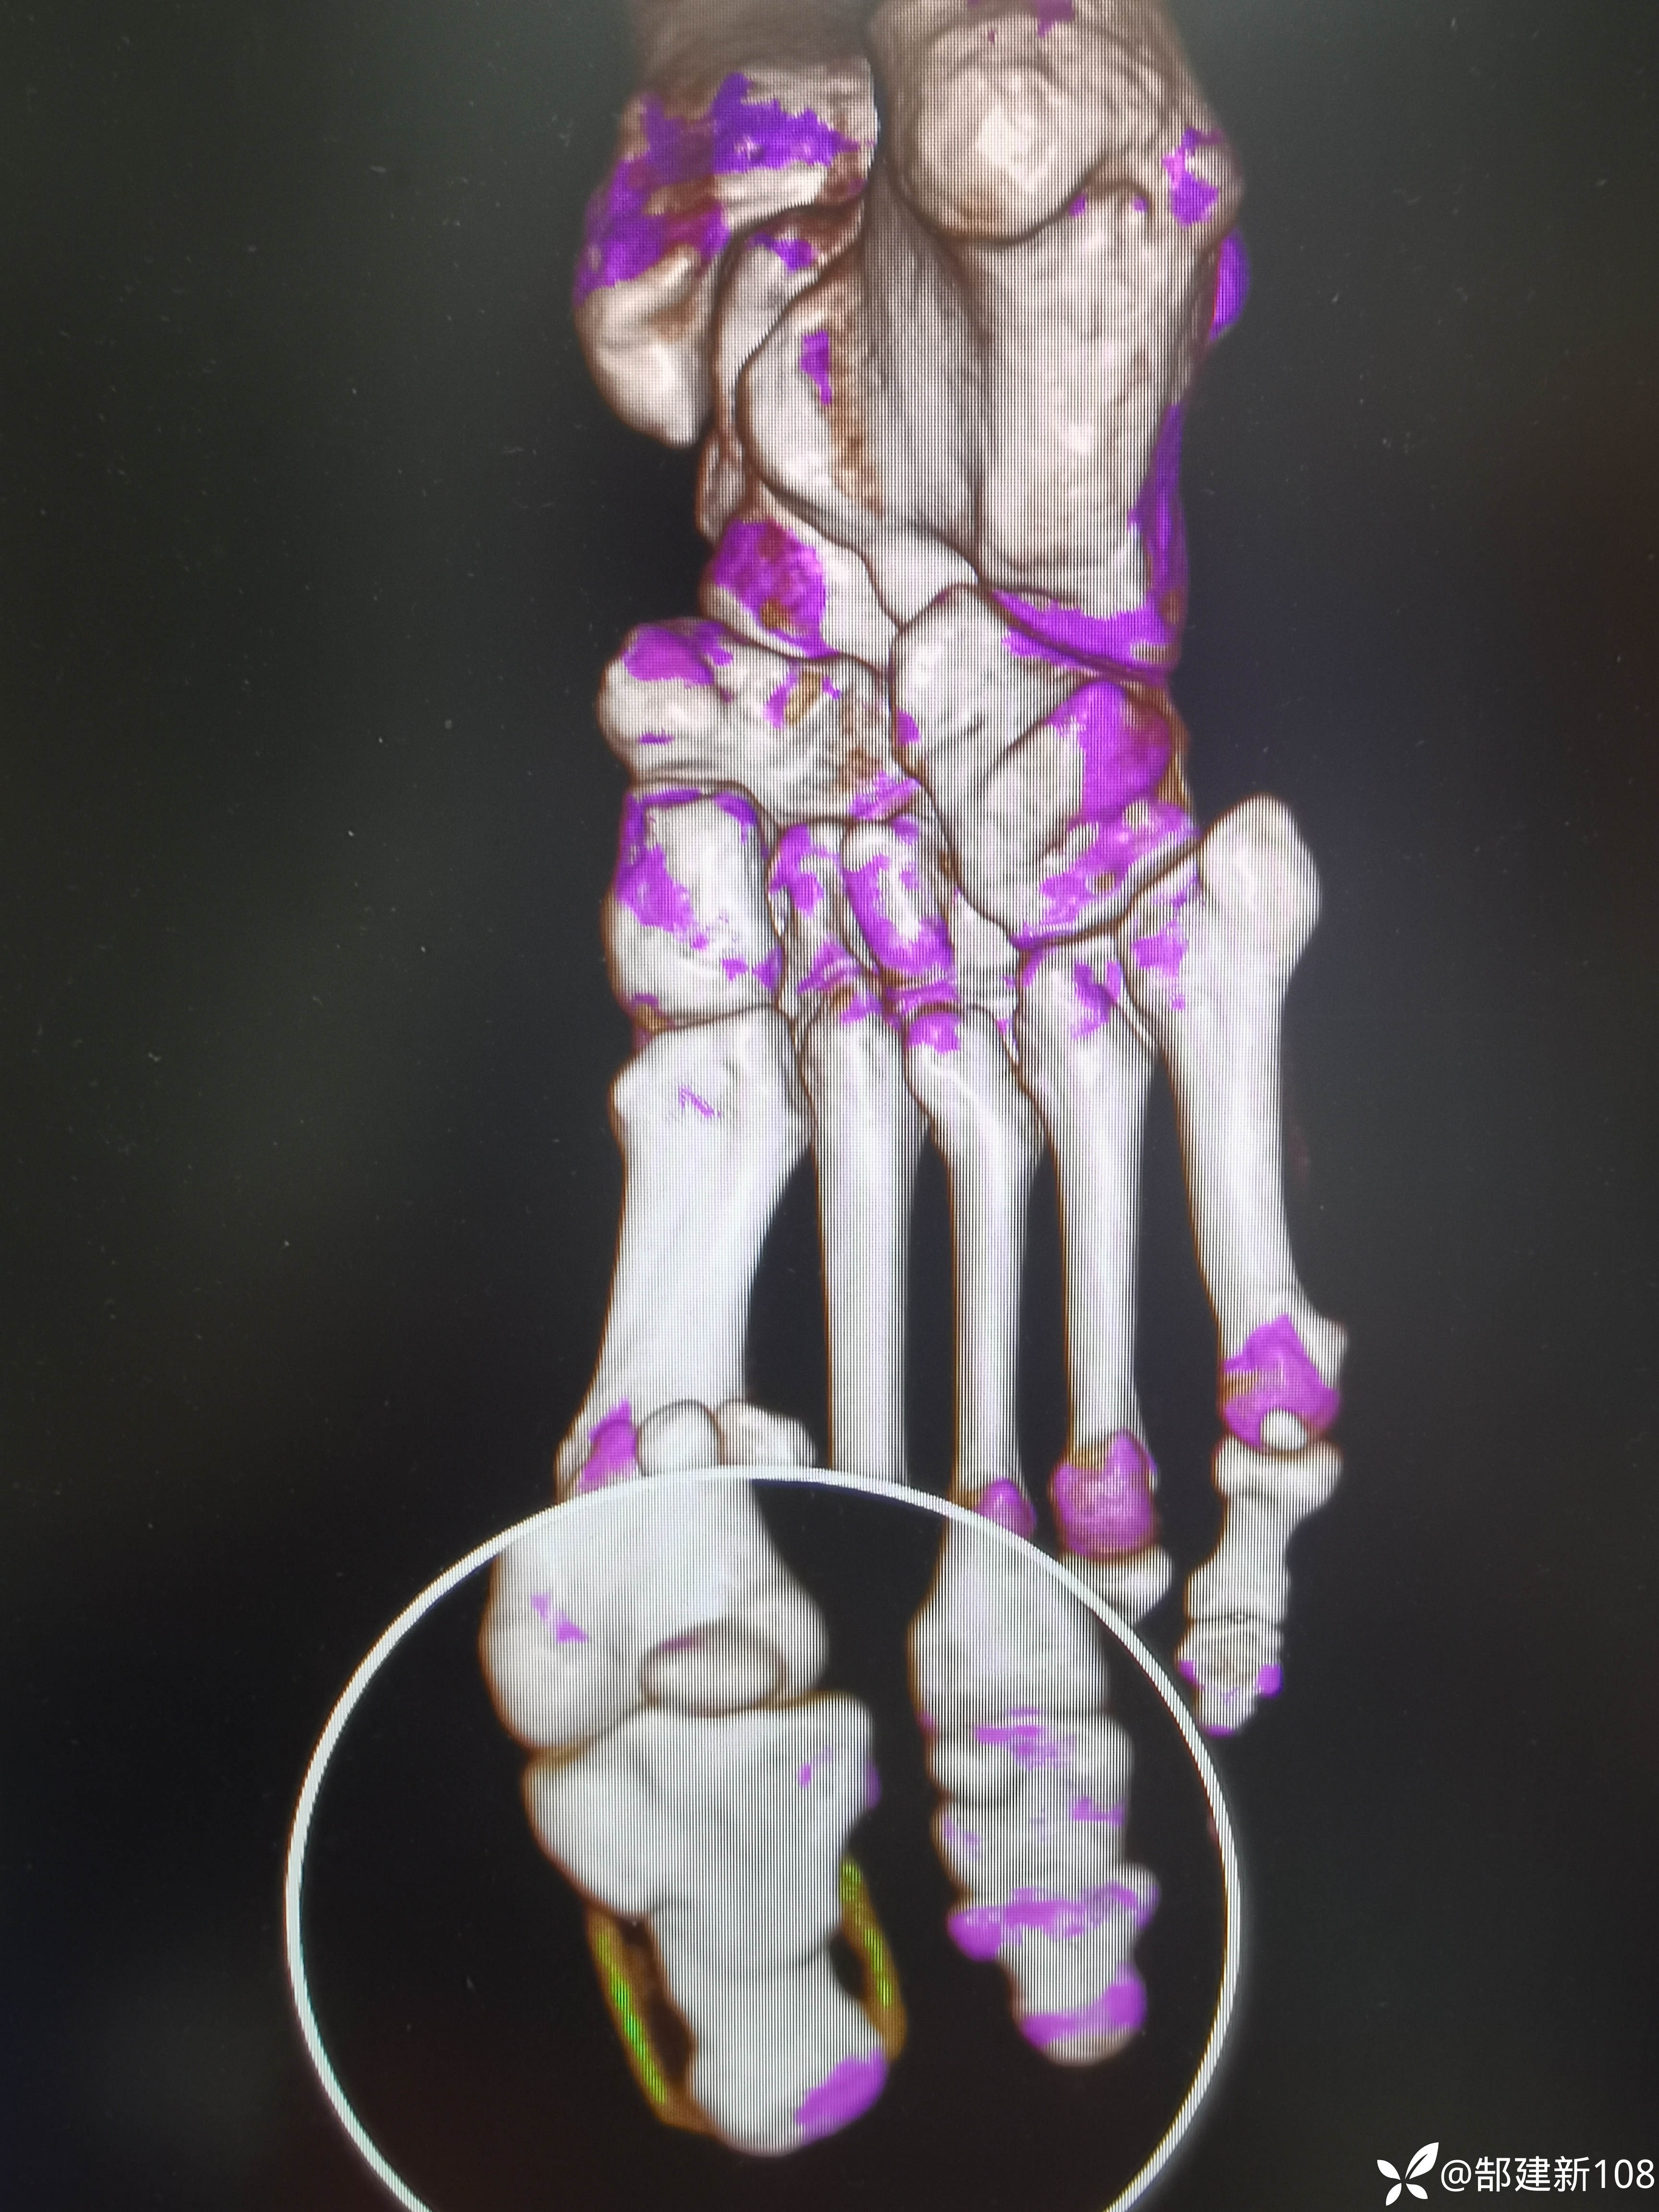

患者男,45岁,尿酸增高3年,足部发作疼痛3天。

筛查早期痛风石可以用双源CT来帮忙,能量成像伪彩色查到绿色的地方可以用读片放大镜或缩放功能可以发现小米粒大小的痛风石。